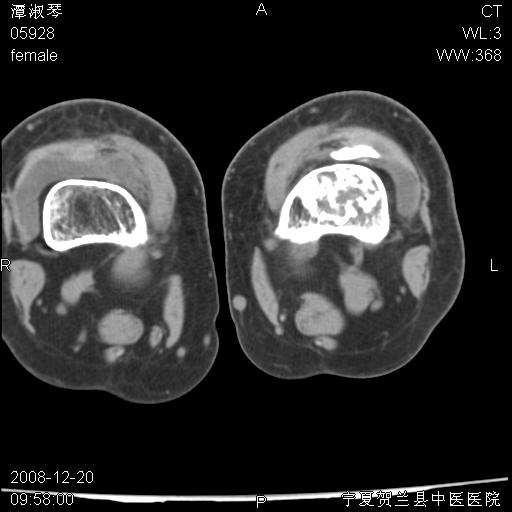

标题: CT17526:请各位看看是啥?

内生软骨瘤?骨梗死?

考虑内生软骨瘤可能性大

考虑-----骨梗死+退变

支持骨梗死,退行性骨关节病,膝关节积液.

考虑骨梗死可能性大

骨梗死可能性大

左股骨下段骨梗死。双膝退变。

左胫骨下端松质骨及髓腔内可见点片状高密度灶,骨皮质无明显膨胀及变薄。病变范围较长。支持骨梗死,退行性骨关节病,膝关节积液